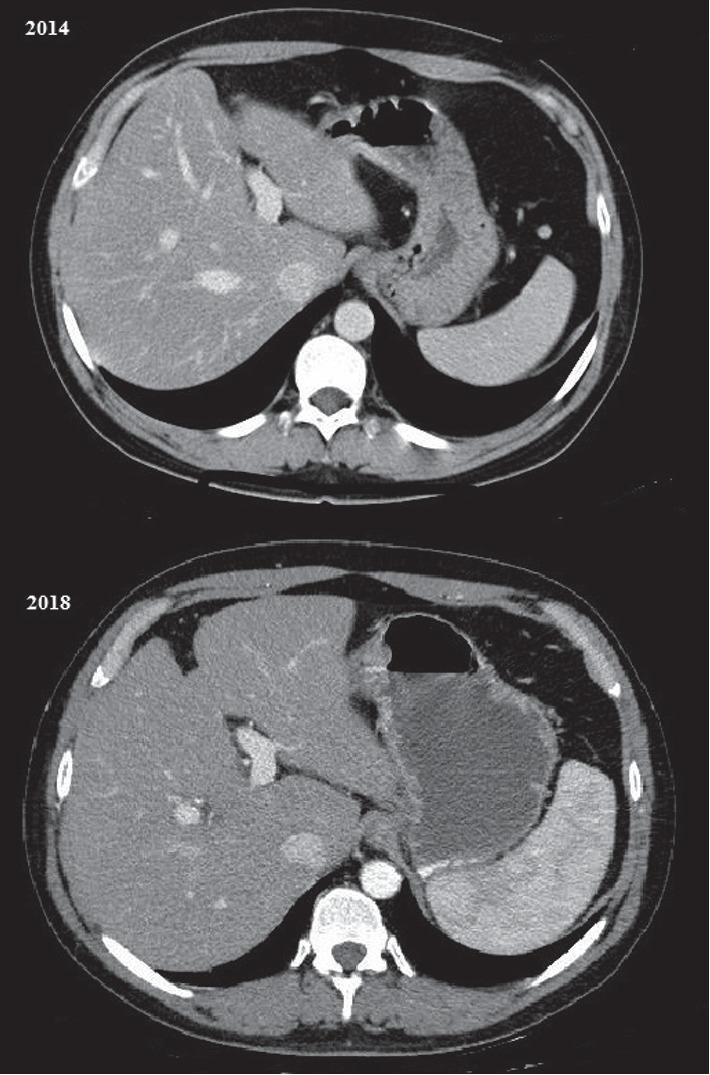

Azathioprine is a cornerstone of the therapy of Crohn's disease. Unfortunately, infections and malignancies are relatively common adverse effects related to this drug; however, cirrhosis is exceptionally reported as a side effect. We report the case of a 49-year-old male patient with ileocolonic steno-penetrating Crohn's disease who developed hepatic cirrhosis while treated with azathioprine. After taking azathioprine for 3 years with regular follow-up, he developed pancytopenia, and liver cirrhosis was diagnosed with ultrasound, abdomen computed tomography scan, transient elastography, and liver biopsy. As all other causes of liver damage were excluded, azathioprine was believed to be the cause of liver injury and therefore was interrupted.

硫唑嘌呤是克罗恩病治疗的基石。不幸的是,感染和恶性肿瘤是与该药物相关的相对常见的不良反应;然而,肝硬化作为一种副作用的报道极为罕见。我们报告一例49岁男性患者,患有回结肠狭窄穿透型克罗恩病,在接受硫唑嘌呤治疗时发生了肝硬化。在规律随访服用硫唑嘌呤3年后,他出现了全血细胞减少,通过超声、腹部计算机断层扫描、瞬时弹性成像和肝活检诊断为肝硬化。由于排除了所有其他肝损伤原因,认为硫唑嘌呤是肝损伤的原因,因此停用了该药。